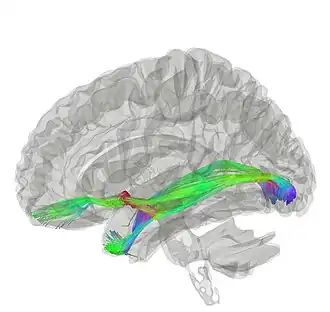

![]() Tractography of anterior commissure | |

The functionality of the anterior commissure is still not completely understood. Researchers have implicated it in functions ranging from colour perception to attention. One such study supported colour perception in callosal agenesis (those born without a corpus callosum; Barr & Corballis, 2002).[3] Other studies have built on this to imply that the anterior commissure can be a compensatory pathway in those without a corpus callosum, presenting diffusion tensor imaging (DTI) techniques to better elucidate the anterior commissure and how it might be implicated in various functions (Winter & Franz, 2014).[2]